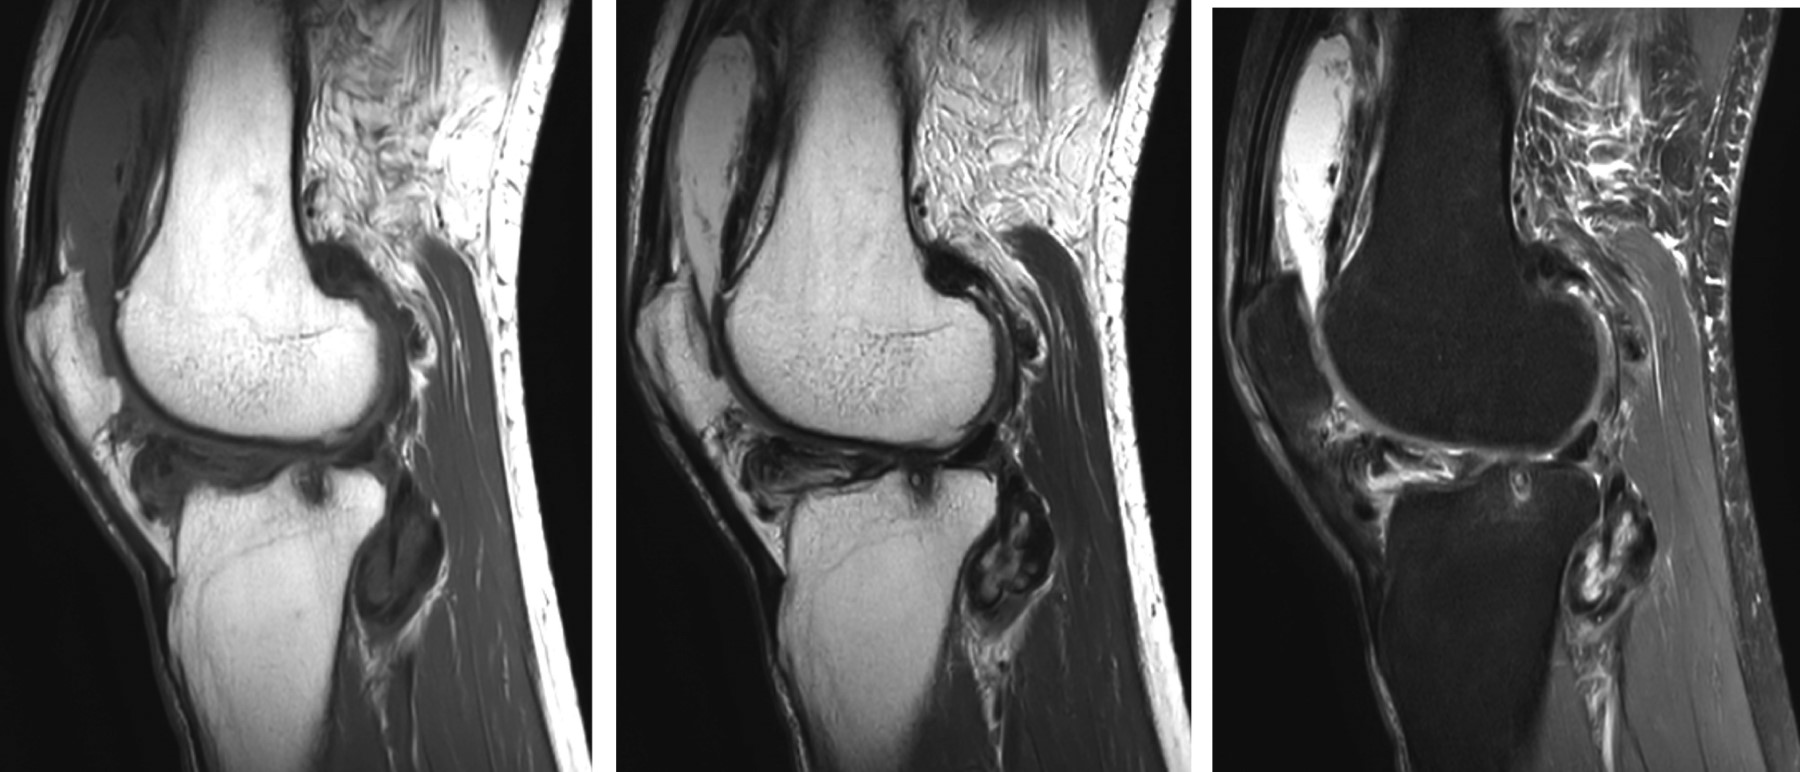

Los hallazgos radiológicos suelen ser patognomónicos. Los hallazgos en la resonancia magnética son más variables y dependen del grado de mineralización; sin embargo, el patrón más común (77% de los casos) muestra una intensidad de señal baja a intermedia en T1 y una intensidad de señal muy alta en T2, con calcificaciones hipointensas.5

Se realizó estudio de resonancia magnética (Figura 1), en el que se identificó aumento de volumen de los tejidos blandos y aumento de la cantidad de líquido sinovial, el cual se observa heterogéneo, con presencia en su interior de imágenes ovoides, de bordes bien definidos y de baja intensidad de señal en T1 y T2. Se observa afectación del compartimento posterior, posterior a las fibras del ligamento cruzado posterior, posterior al borde posterolateral de la tibia, en la topografía de la grasa de Hoffa, posterior al cóndilo femoral lateral y en la región suprapatelar.

Figura 1